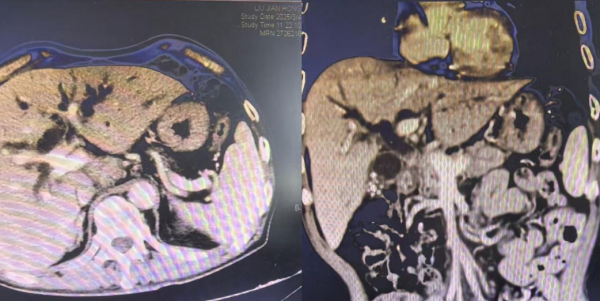

患者胆总管受压,肝内胆管重度扩张

有什么方案能够同时解决患者“内科药物治疗效果不佳,传统外科手术治疗又难以耐受”难题,且还要控制肿瘤的局部进展呢?李岳勇带领肿瘤介入团队深入研判,提出了“支架开通+粒子放疗”的微创介入方案,即通过胆道支架快速解除胆道梗阻,同步植入碘125粒子对肿瘤病灶实施精准持续放疗,实现“疏通”与“控瘤”双重治疗目标。